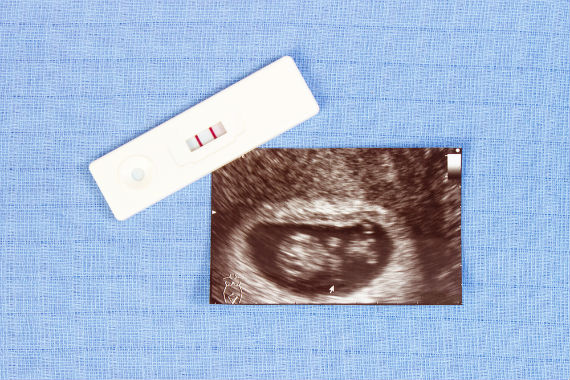

วิธีสังเกตว่าท้องหรือไม่ ช่วงเวลาที่พลาดมักจะเป็นเบาะแสแรกที่ผู้หญิงอาจจะตั้งครรภ์ ทุกวันนี้ผู้หญิงหลายคนใช้การทดสอบการตั้งครรภ์ที่บ้าน ซึ่งเป็นวิธีตรวจสอบขั้นพื้นฐานเมื่อคุณมีความสงสัยว่าตัวเองตั้งตั้งครรภ์หรือไม่? หากคุณอยากทราบว่าตัวเองกำลังท้องหรือตั้งครรภ์หรือไม่นั้น คุณสามารถซื้อที่ตรวจ “ชุดทดสอบการตั้งครรภ์” มาตรวจเองที่บ้านได้ตั้งแต่วันแรกที่คุณมีเพศสัมพันธ์แบบไม่ป้องกัน และถ้าจะให้เห็นผลอย่างชัดเจน เราแนะนำให้รอประมาณ 7 วันหลังจากที่คุณเพศสัมพันธ์ค่ะ

อาการที่บ่งบอกว่าท้อง : ประจำเดือนคุณขาด เป็นสัญญาณแรก ที่บ่งบอกว่า คุณอาจกำลังตั้งครรภ์ แต่ยังมีอาการอื่น ๆ อีก 4 อย่าง ที่บ่งชี้ว่าคุณกำลังตั้งครรภ์ โดย 4 อาการที่บ่งบอกว่าคุณท้อง กดท้องยังไงให้รู้ว่าท้อง จับท้องยังไงให้รู้ว่าท้อง คุณแม่สังเกตได้ดังนี้ ได้แก่